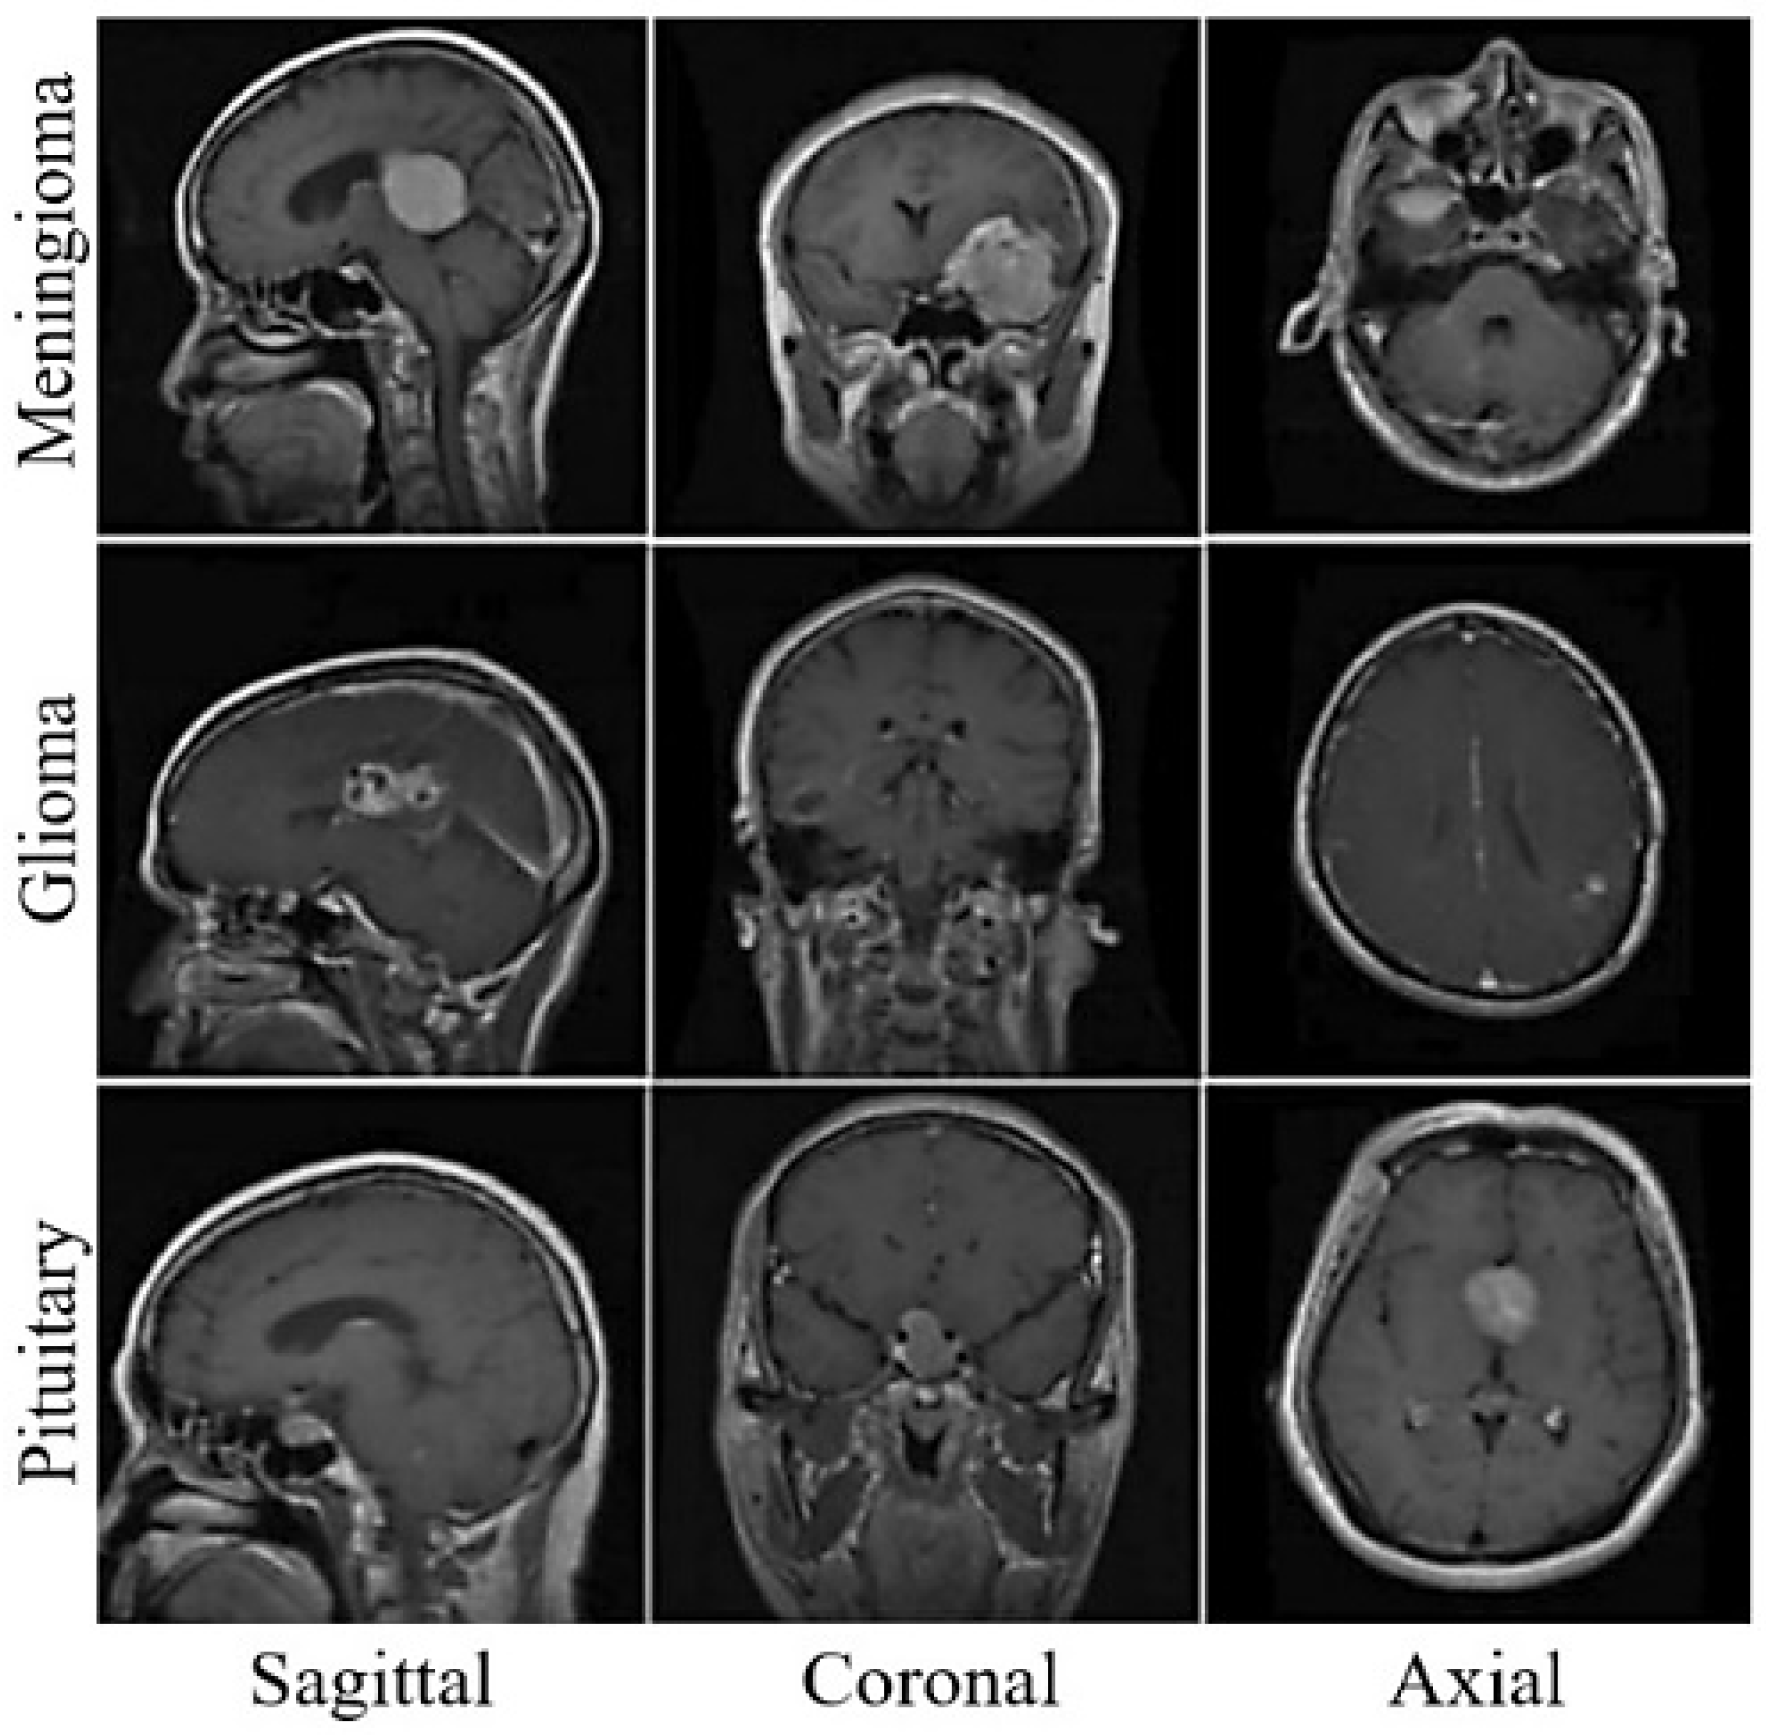

4.1. Dataset